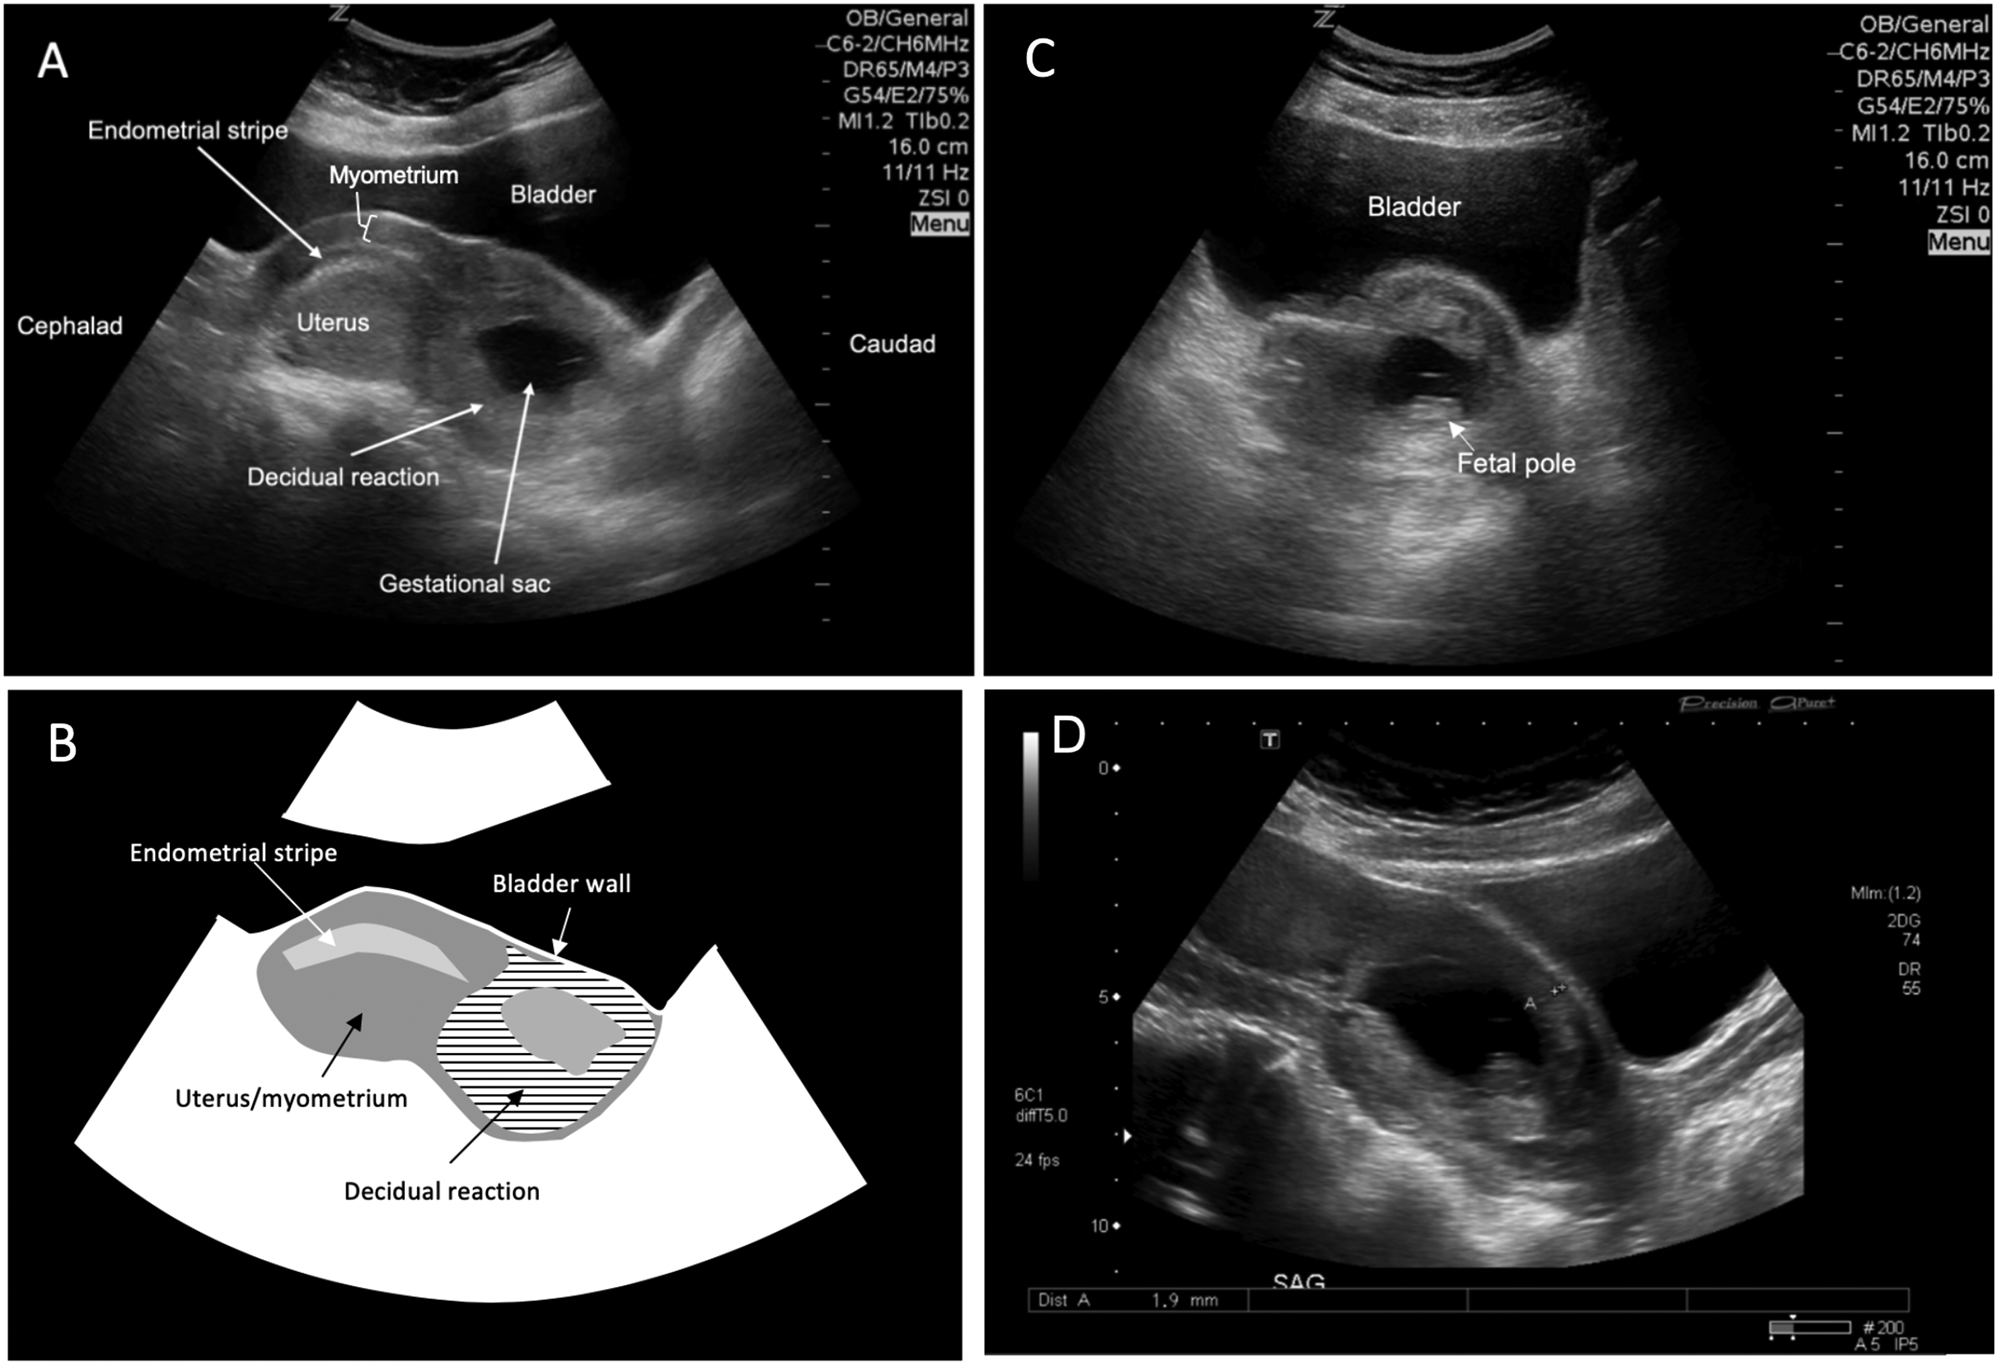

A point-of-care ultrasound examination was performed in the emergency department by the emergency physician. A 6-2 MHz curvilinear probe with the obstetric preset selected was placed in the longitudinal orientation cephalad to the pubic symphysis. The scan revealed a gestational sac with surrounding decidual reaction immediately adjacent to the bladder (Figures 1A and 1B). This was positioned in the lower segment of the uterus without a typical-appearing homogeneous myometrium surrounding all sides. A transverse probe orientation revealed a fetal pole within the gestational sac and again demonstrated an absence of myometrium (Figure 1C). An M-mode tracing revealed a heart rate of 171 beats per minute, signifying a live pregnancy. No free fluid was visualized in the pelvis, nor in the patient's right upper quadrant. These findings were concerning for a live ectopic pregnancy within the anterior wall of the uterus.

Figure 1. (A) Longitudinal point-of-care ultrasound scan positioned cephalad to the pubis reveals a gestational sac within the lower anterior aspect of the uterus adjacent to the bladder and absence of normal myometrium surrounding the gestational sac. (B) Schematic representation of Figure 1A, denoting the relationship of myometrium, decidual reaction, and bladder wall. (C) Transverse point-of-care ultrasound scan demonstrating a fetal pole within the gestational sac and heterogeneous surrounding tissue. (D) Consultative transabdominal longitudinal ultrasound showing a myometrial thickness of 1.9 mm anterior to the gestational sac.

A consultative ultrasound scan of the pelvis and abdomen was ordered, and obstetrical consultation was requested. The ultrasound confirmed a cesarean scar ectopic, with myometrial thinning of 1–2 millimetres overlying the anterior aspect of the pregnancy (Figure 1D). The patient remained stable and the decision was made by the obstetrical consultant to perform a staged procedure. The patient underwent an ultrasound-guided transvaginal potassium-chloride injection directly into the gestational sac with aspiration of its contents and subsequent laparoscopically guided hysteroscopy with dilatation and curettage. She was discharged in good condition.

In our case, 4 of 5 criteria for intrauterine pregnancy diagnosis by point-of-care ultrasound diagnosis were met (gestational sac, decidual reaction, yolk sac/heart rate, bladder-uterine adjacency). However, the images reveal a lack of visible myometrium surrounding the gestational sac, particularly on the aspect in contact with the bladder. Further scrutiny also reveals that, unlike a normal intrauterine pregnancy, the cesarean scar ectopic is eccentrically located, being positioned lower in the uterus than the expected site of implantation. In our case, this is the most obviously abnormal feature.